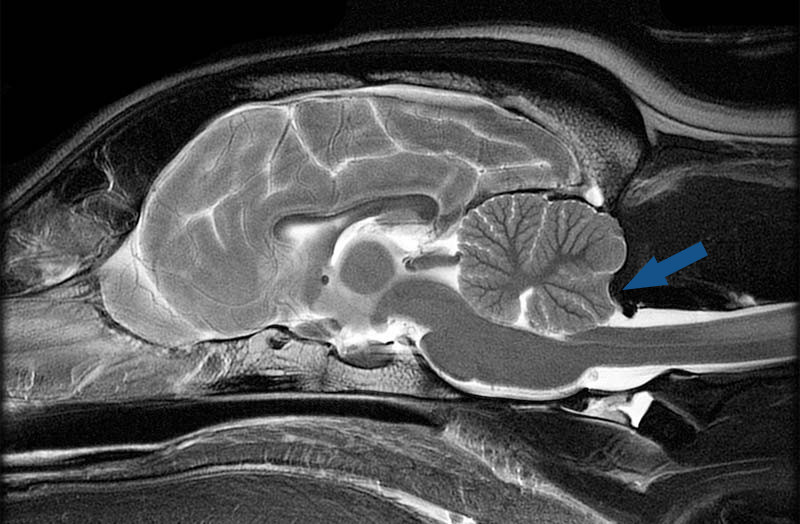

Кавалер-кинг-чарльз-спаниели

Эта порода отразила моду на уменьшение размера головы при сохранении больших «кукольных» глаз, что привело к аномалии Киари и сирингомиелии: черепная коробка собак стала слишком тесной для мозга. Главный симптом — невропатическая боль: собаки могут внезапно вскрикивать без видимой причины, бояться прикосновений к голове, шее или ушам. Характерный признак — фантомное чесание, когда собака двигает лапой в воздухе, не касаясь шеи. Это реакция не на зуд, а на болевые прострелы в спинном мозге, похожие на удар током.

Аномалия Киари. Фото: vethospital.ru

Владельцы склонны списывать боль своих питомцев на «странности характера», пока нарушения работы спинного мозга не приводят к тому, что собака может спать и есть только с задранной головой. В отдельных случаях все заканчивается слабостью конечностей и параличом. Многие представители этой породы могут прожить всю жизнь с облегченными и практически незаметными симптомами, но почти половина из них страдает от подобных недугов.